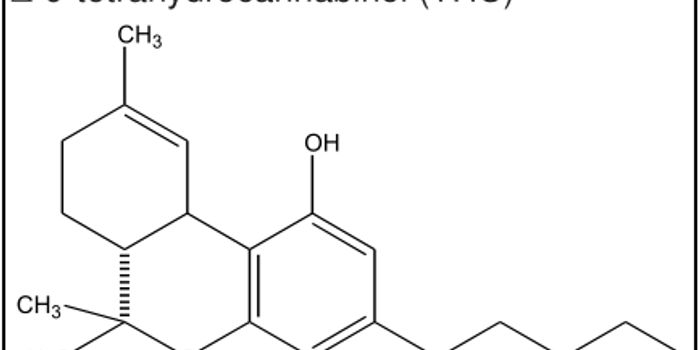

JUN 23, 2016Cannabis SciencesThe question of whether or not to legalize marijuana is controversial, with experts weighing in on both sides of the iss ...

JUN 09, 2016Cannabis SciencesAs marijuana proves itself effective in treating a multitude of diseases, researchers are looking for problems associate ...

APR 20, 2016Cannabis SciencesHardly a week goes by without some news of new research into concussion injuries. Most of the focus is on the NFL and th ...

FEB 16, 2016Cannabis SciencesA variation of the ATK1 gene has been linked to people who develop psychosis. ATK1 encodes a “kinesin-like motor p ...

JAN 14, 2016Cannabis SciencesScientists have known for a while that marijuana definitely affects brain chemistry, function and structure. Studies hav ...

DEC 03, 2015Cannabis SciencesStronger is not always better. While it’s good to have strong muscles and bones, when it comes to pot, the strong ...

APR 09, 2015Cannabis SciencesIf you want the benefits of medical marijuana without the "unwanted side effects" of cannabis, new research could leave ...